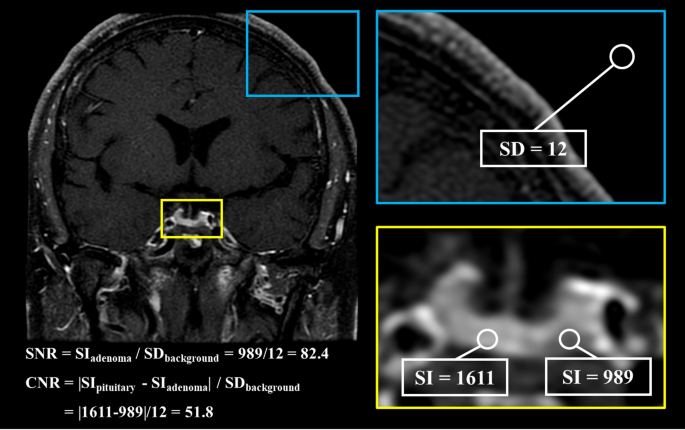

Biochemical testing confirmed ACTH-dependent Cushing syndrome (Table 1). Cortisol levels following overnight and 48-hour dexamethasone suppression were elevated at 8 µg/dL (SI: 219 nmol/L) and 16 µg/dL (SI: 434 nmol/L), respectively (reference range: < 1.8 µg/dL [SI: < 50 nmol/L]). Plasma ACTH concentrations ranged from 36 to 55 ng/L (SI: 7.9-12.1 pmol/L) (reference range: 10-30 ng/L [SI: 2.2-6.6 pmol/L]), consistent with an ACTH-driven process. Urinary free cortisol (UFC) was markedly elevated at 690.95 µg/24 hours (SI: 1907 nmol/24 hours) (reference range: 18-98 µg/24 hours [SI: 50-270 nmol/24 hours]). Late-night salivary cortisol and cortisone levels were also elevated at 0.95 µg/dL (SI: 26.2 nmol/L) (reference range: < 0.09 µg/dL [SI: < 2.6 nmol/L]) and 2.7 µg/dL (SI: 74.5 nmol/L) (reference range: < 0.7 µg/dL [SI: < 18 nmol/L]) respectively. Inferior petrosal sinus sampling excluded an ectopic source of ACTH production (central-to-peripheral ACTH ratio: baseline 18.60, 0 minutes 18.4, peak at 2 minutes 94.9, 5 minutes 42.4, 10 minutes 22.3) (Table 2). However, pituitary MRI findings were inconclusive, with no definite adenoma identified. In addition, the left intracavernous carotid artery encroached medially, creating a narrow intercarotid window with distortion of normal pituitary anatomy (Fig. 1). Given these findings, the decision was made to initiate cortisol-lowering therapy and to reassess imaging appearances after a period of biochemical normalization.

Pituitary MRI at initial presentation. No discrete adenoma is visible on T1-weighted coronal precontrast (A) and postcontrast (B), T2-weighted coronal (C), and T1-weighted sagittal postcontrast (D) sequences. The sellar anatomy appears asymmetric, consistent with a medially positioned left internal carotid artery.